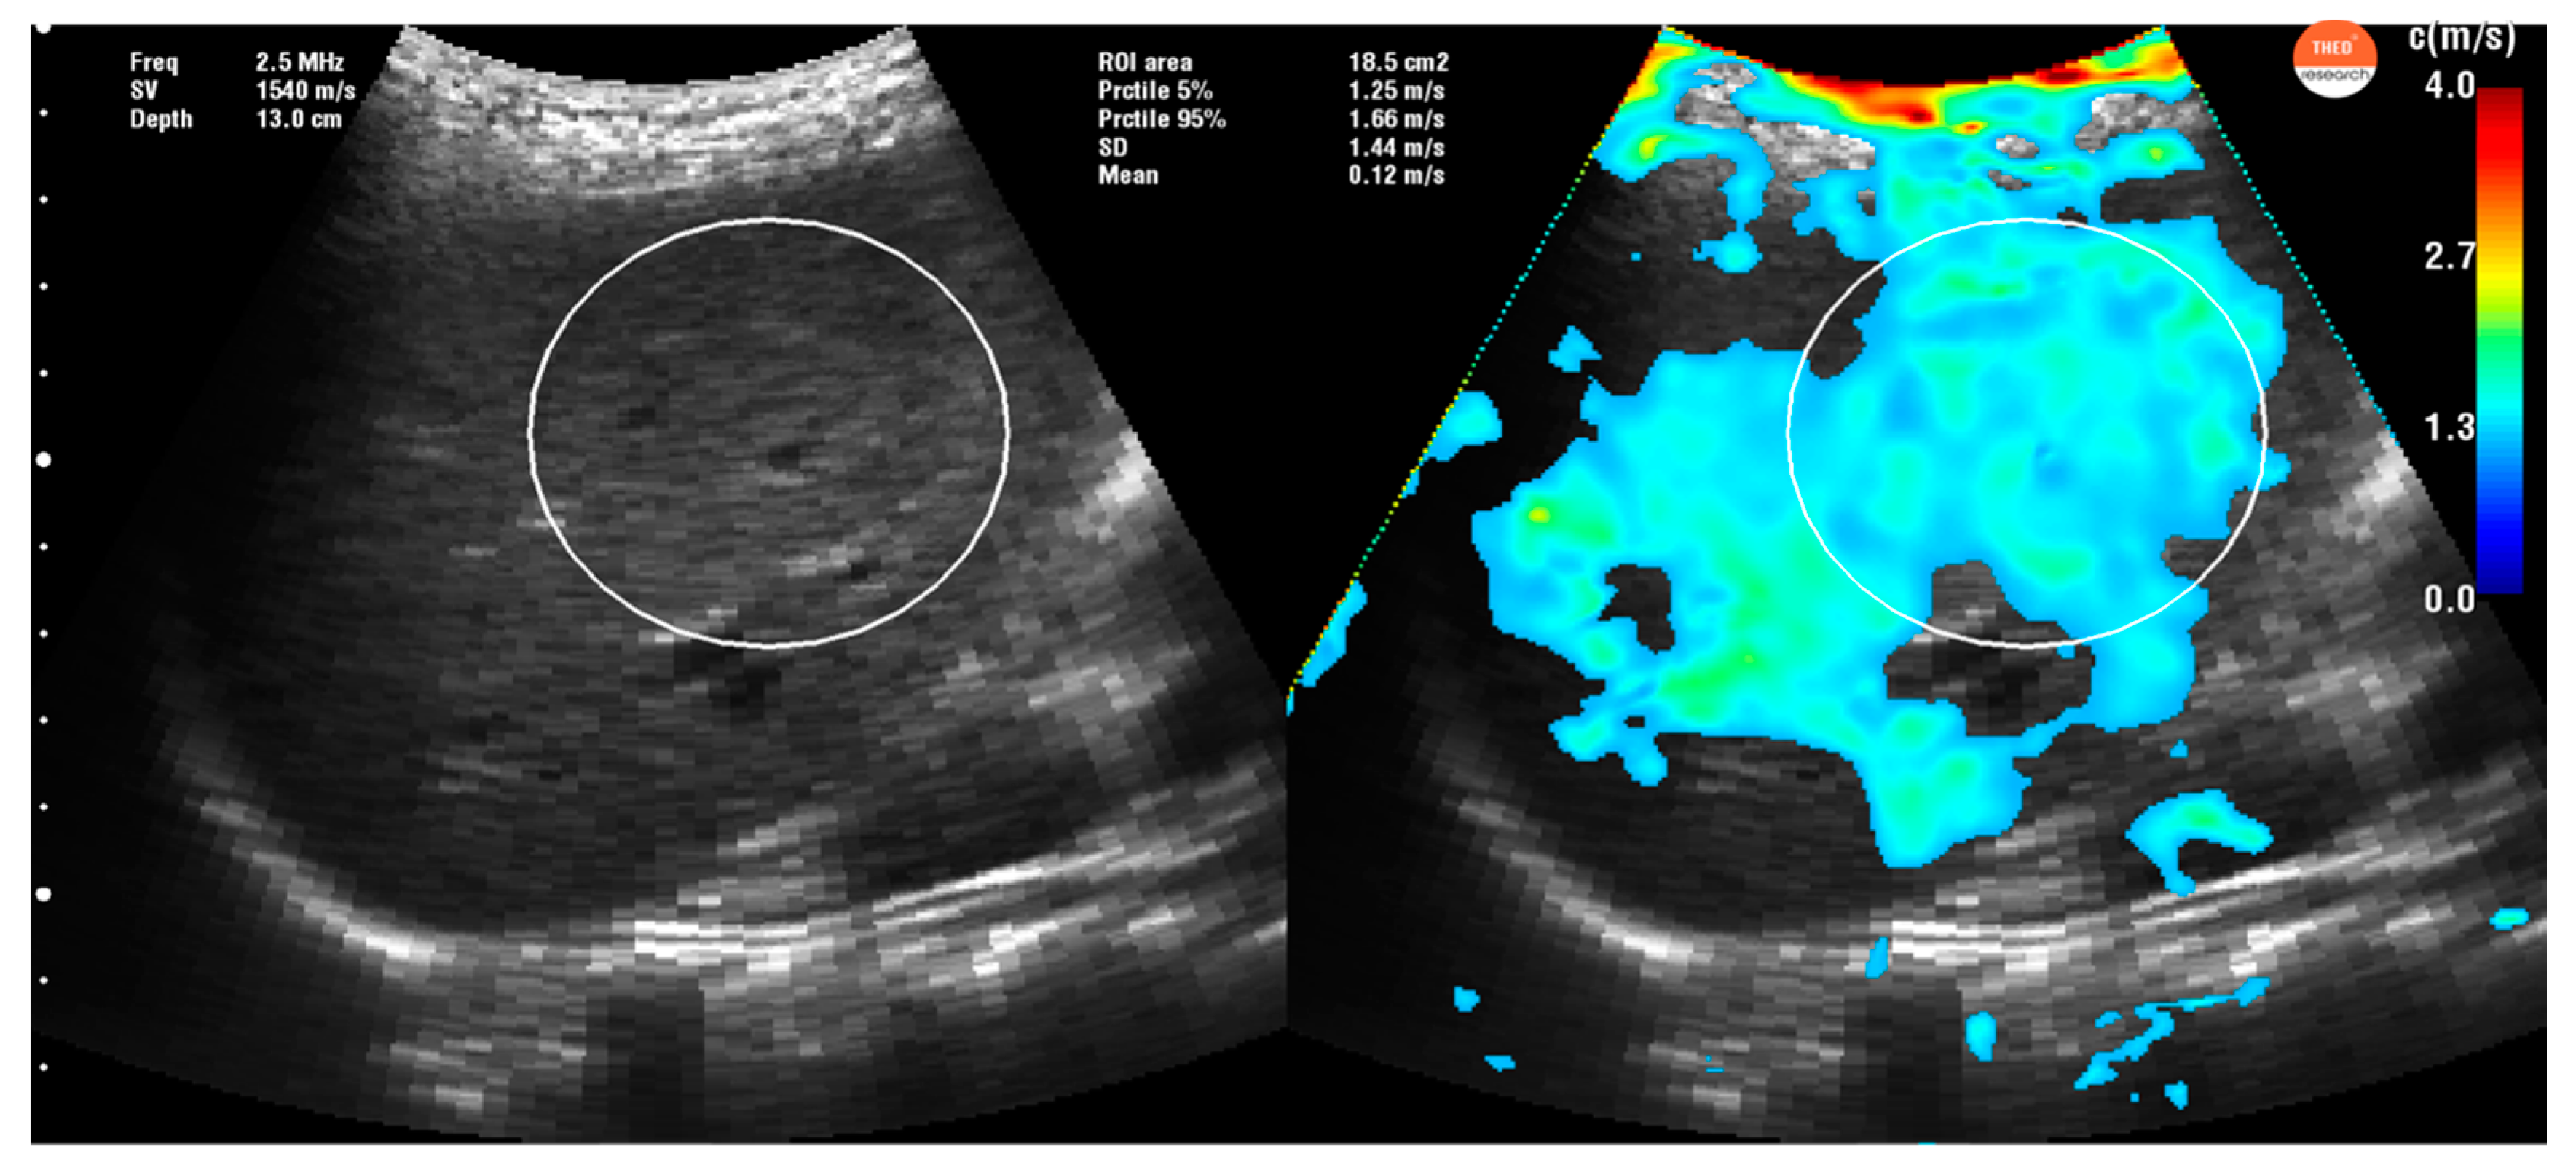

2.3. Time Harmonic Elastography Evaluation